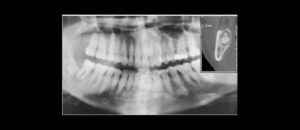

El conocimiento de la bifurcación del conducto dentario inferior (CDI) es importante, ya que ofrece posibles explicaciones para el fracaso de la anestesia, y para